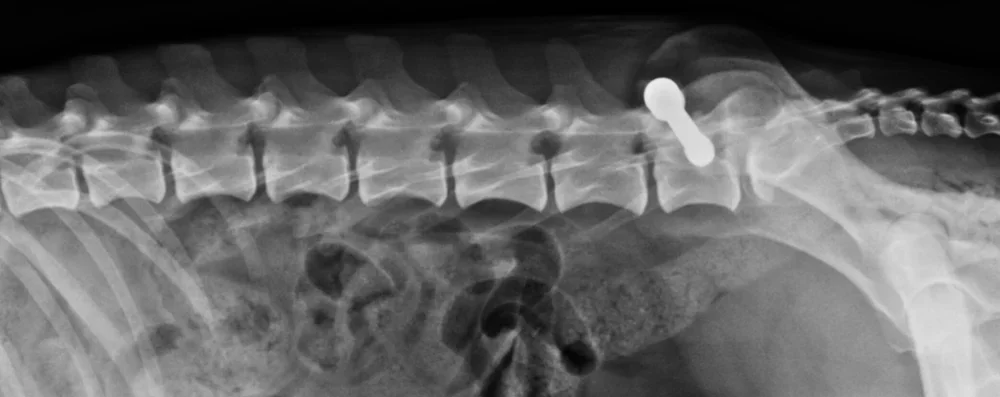

Røntgen

Røntgenundersøkelse

Vi har moderne digitalt røntgensystem og utfører alle typer røntgen av bryst, skjelett og buk. Dette kan benyttes eks. ved akutt oppstått skade eller sykdom, smerter og halthet, skjelettlidelser, anstrengt respirasjon, drektighet eller HD røntgen. Et røntgenbilde kan gi verdifull informasjon som er vanskelig å evaluere på annen måte.